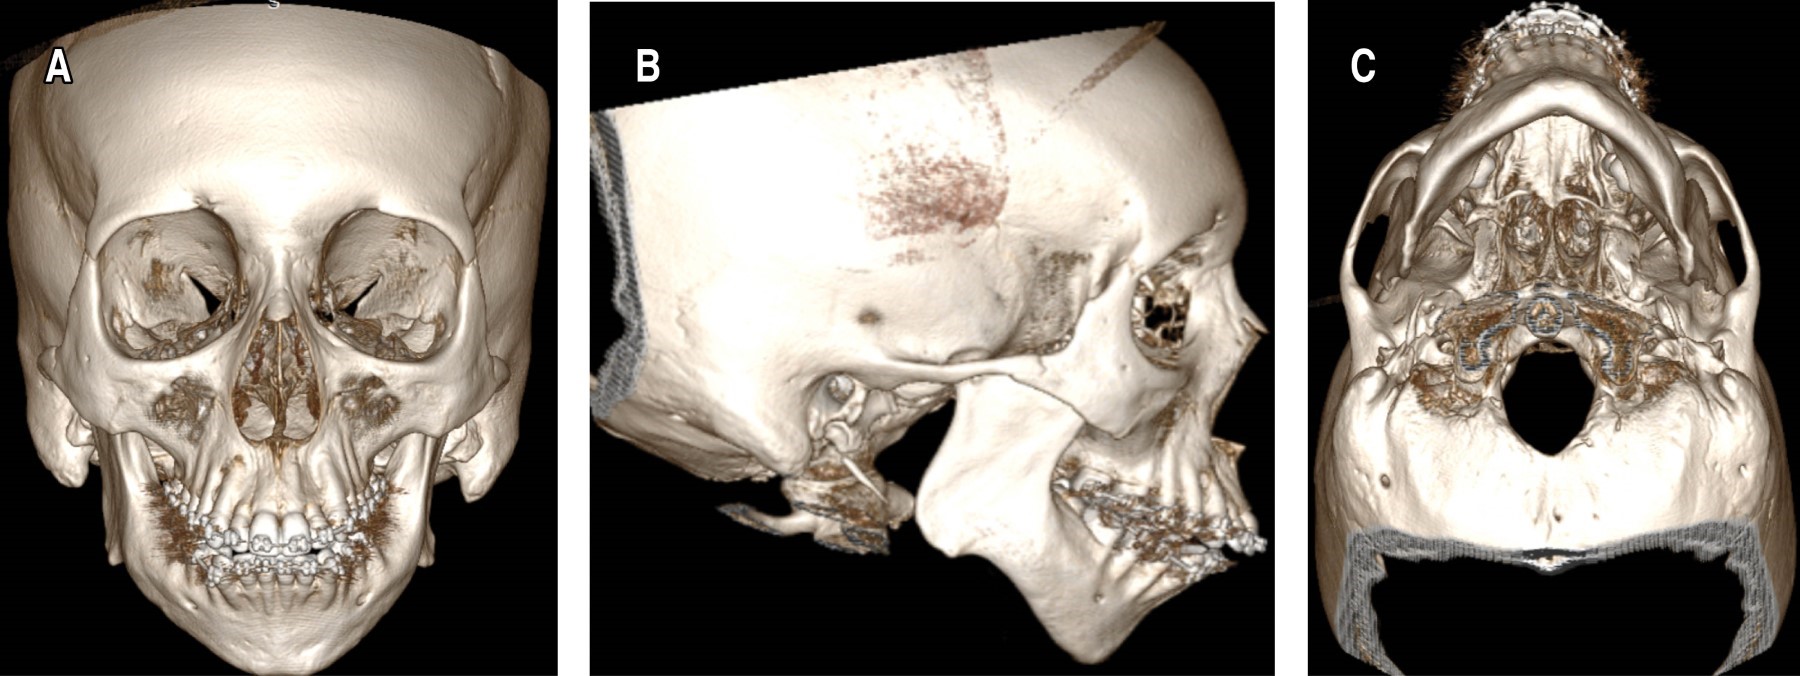

Paciente de sexo femenino de 39 años de edad, con antecedente de hipotiroidismo congénito y sin antecedentes hereditarios relevantes. Consulta por asimetría facial, maloclusión y sospecha de apnea del sueño. Al examen físico se evidencia una marcada micrognatia y microgenia que contribuyen a una retrusión mandibular severa. La evaluación intraoral reveló una clase II esqueletal, exceso vertical del maxilar superior, mordida abierta anterior y contacto molar limitado. Adicionalmente, se observó una angulación del plano oclusal aumentada, torque negativo de los incisivos e incompetencia labial (Figura 1).

Se realiza tomografía computada que revela micrognatia asociada con aplasia de los cóndilos mandibulares con aplanamiento bilateral de las cavidades glenoideas y ausencia del tubérculo articular en su porción medial acompañado de luxación bilateral (Figura 2). Adicionalmente se realiza polisomnografía, la cual no evidencia alteraciones, descartando la posibilidad de síndrome de apnea obstructiva del sueño (SAHOS).

Figura 1

Figura 2